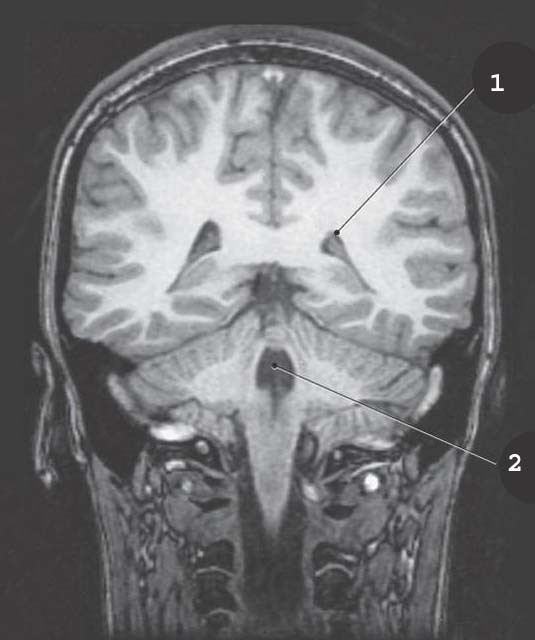

1

Midbrain

Longitudinal Fissure

2

corpus collosum genu

3

septum pellucidum

4

3rd ventricle

5

corpus collosum splenium

6

corpus collosum rostrum

Thalamus

Pineal gland

cerbral aqueduct